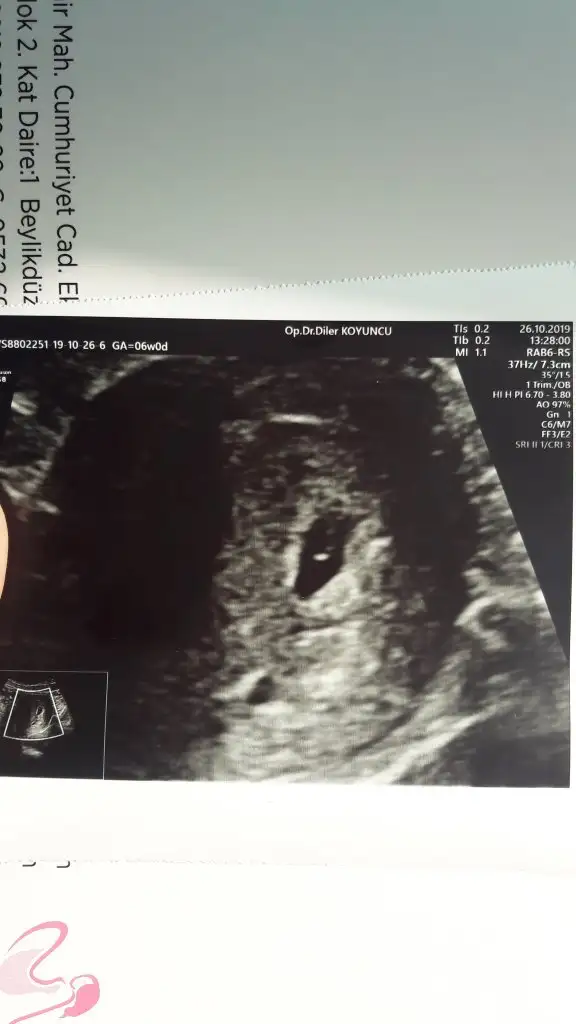

Arkadaşlar hamiş olan anne adaylarımıza hayırlı bir hamilelik dilerim. Bende 5 hafta 6 günlük hamileyim ilk kontrolüm gitmiş bulunmaktayım.Doktorum erkek bebek kesesine benziyor tabi hazırlık yapmayın sakın ha dedi. Bende konuyu araştırırken bu teoriye denk geldim yorumlarmısınız acaba.

ne demekmiş erkek bebek kesesi? Sordunuz mu nerden anladınız diye? Yuvarlak olması mı?